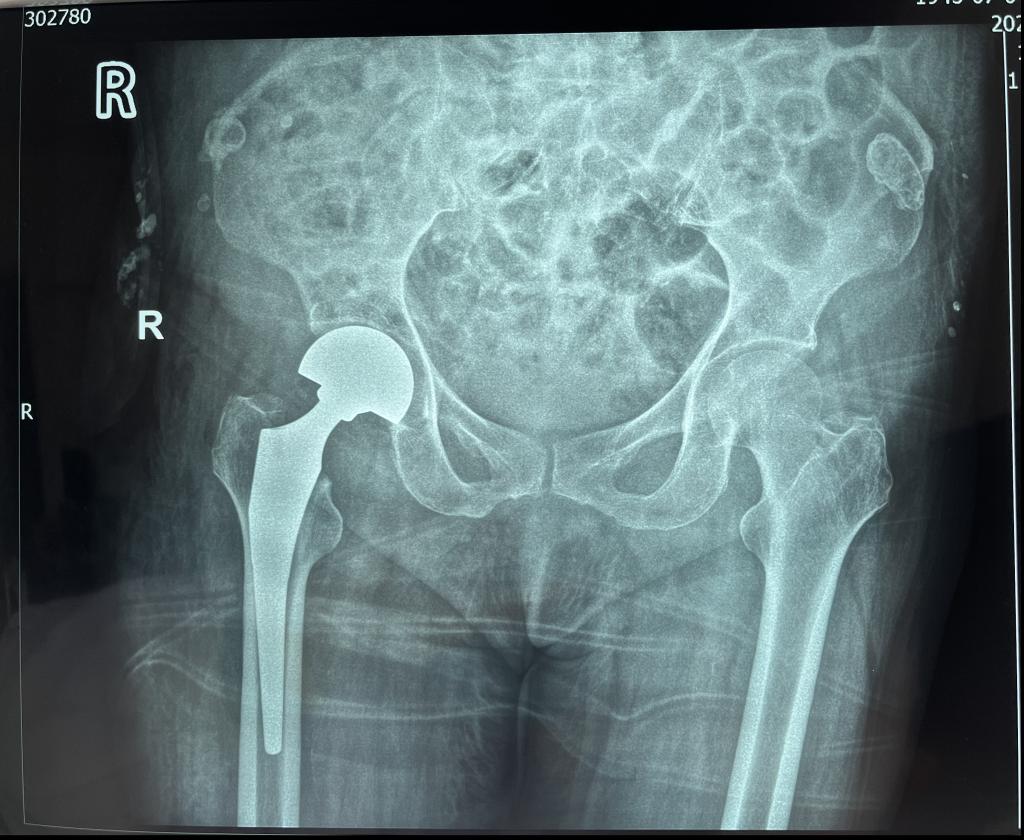

近日,MILAN.COM骨三科连续收住多位因跌倒摔伤导致髋部骨折的老年患者,在当地医院检查后均被告知需等待较长时间方能手术,家属听闻MILAN.COM为老年髋部骨折患者开通了绿色通道,24小时内即可手术,遂来我院。入院后骨三科医疗团队立即启动老年髋部骨折绿色通道并全面评估患者病情,在科室的多方协调下,患者入院后3小时即在全身麻醉下进行了微创闭合复位内固定术,再一次刷新了手术准备时长的记录。

MILAN.COM骨三科暨骨关节科是以关节疾病为主,涉及关节病、运动医学及关节周围骨折、老年脆性骨折为亚专业特征的学科。科室针对因骨质疏松引起的老年股骨颈骨折、股骨转子间骨折、胸腰椎体压缩性骨折等已成功开展数百例老年髋部骨折绿色急诊手术通道、微创人工股骨头置换术、微创股骨骨折内固定术以及经皮椎体成形术,并取得不菲成绩。